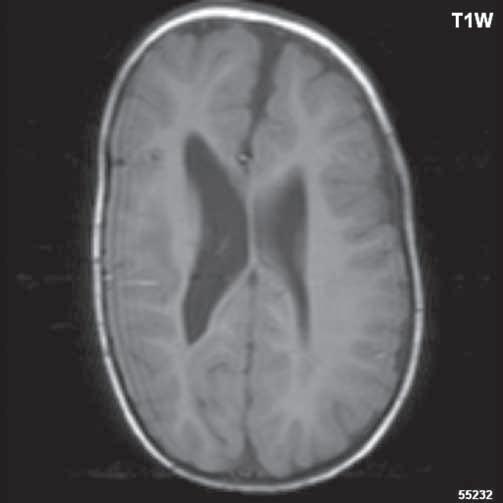

Často agenezi/dysgenezi corpus callosum doprovází středočárový lipom nebo cysta. Při mediálním okraji postranních mozkových komor zobrazíme Probstovy provazce, což jsou axony neuronů, které za normálních okolnosti přecházejí přes corpus callosum do druhé mozkové hemisféry. Deficit bílé hmoty mozkové okcipitálně v okolí postranních komor při absenci corpus callosum je důvodem rozšíření okcipitálních a části parietálních rohů postranních komor – colpocefalie.

Při agenezi corpus callosum CT i MR zobrazí paralelní průběh postranních mozkových komor (oproti fyziologickému

konvergentnímu průběhu) a jejich oddálení, časté rozšíření okcipitálních rohů – colpocefalie, někdy středočárový lipom, cystu. Koronální řezy ukážou rozšíření frontálních rohů postranních komor, III. komora je situována vysoko mezi postranní komory, tvoří jakoby trojzubec, který někteří autoři přirovnávají k přilbě Vikinga. Není patrné septum pellucidum. Častá je přítomnost středočárového lipomu nebo cysty.

Na vnitřní straně postranních komor pozorujeme v T2W obrazu poněkud tmavší strukturu než okolní myelinizovaná vlákna (naopak v T1W obrazu zvýšený signál), Probstovy provazce, axony, které za fyziologických okolností přecházejí přes corpus callosum do kontralaterální hemisféry.

Sagitální řezy nám přinášejí nejvíce informací o corpus callosum. Pozorujeme radiální průběh mozkových sulků ke stropu III. komory na vnitřní straně mozkových hemisfér a naopak nezobrazíme gyrus cinguli. Při parciální agenezi je postiženo především splenium.

Obr. I.1.2a Paralelní postavení postranních komor, kolpocefalie, ageneze corpus callosum

Obr. I.1.2b Ageneze corpus callosum

Obr. I.1.2c Ageneze corpus callosum, frontální rohy postranních komor mají tvar rohů na Vikingské helmě, kraniálně uložená III komora

Obr. I.1.2e Ageneze corpus callosum, frontální rohy postranních komor mají tvar rohů na Vikingské helmě, kraniálně uložená

III komora, Probstovy provazce (šipka)